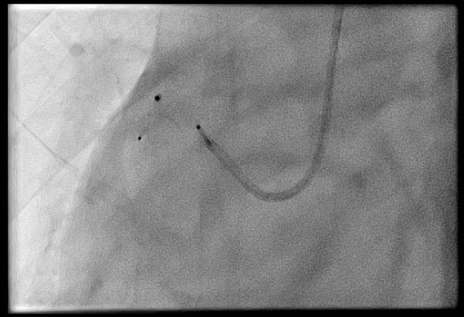

The procedure was performed via left radial artery access. The right coronary fistula was engaged with a 6F AL1 guide catheter. A 5F microcatheter advanced an ASAHI Sion Black wire into the fistula tract. Given the fistula¡¯s large size and high flow, a two-device closure strategy was employed. A 7-mm AMPLATZER Vascular Plug 4 was initially deployed proximally, achieving partial flow reduction. To ensure complete occlusion, an 8-mm AMPLATZER Vascular Plug was subsequently positioned at the ostium. Final angiography confirmed marked flow reduction in the fistula while preserving native RCA flow. The small LAD fistula was left untreated due to minimal shunting. The procedure was completed without complications, and radial hemostasis was achieved.